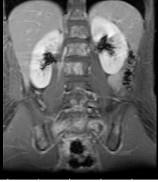

7岁,男,发热、消瘦,数月前触及颈部淋巴结肿大,CT和MR检查如图,请选择最可能的诊断 ( )A.淋巴瘤B.结节病C.淋巴结核...

问题 7岁,男,发热、消瘦,数月前触及颈部淋巴结肿大,CT和MR检查如图,请选择最可能的诊断 ( )

选项 A.淋巴瘤 B.结节病 C.淋巴结核 D.转移性淋巴肿大 E.胸腺瘤

答案 A